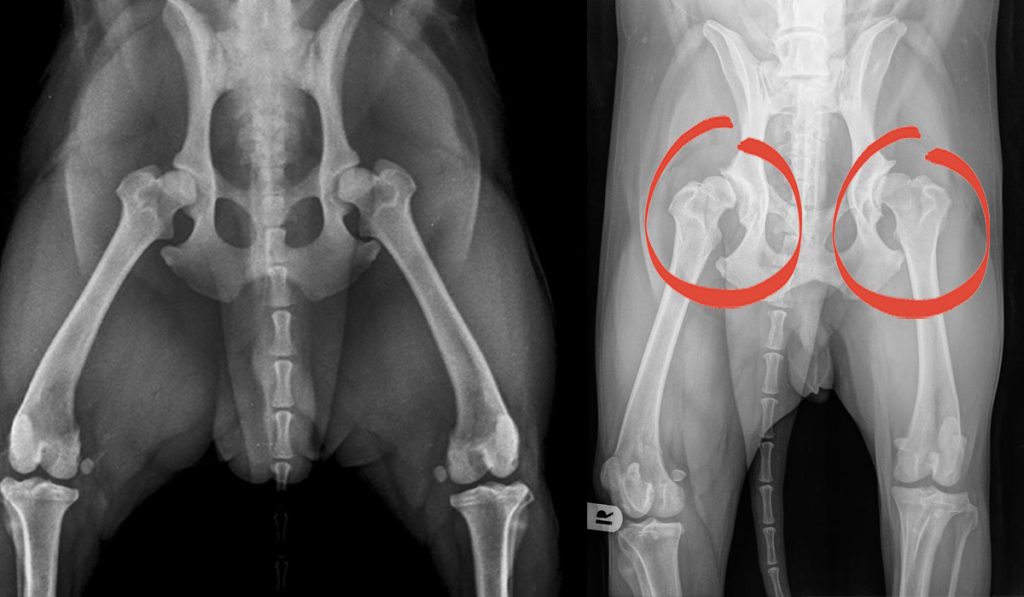

Like many other conditions, hip dysplasia has a wide range of severity, from mild (loose joints) to severe (complete dislocation). Hip dysplasia in babies, also known as developmental dysplasia of the hip (ddh), occurs when a baby’s hip socket (acetabulum) is too shallow to cover the head of the thighbone (femoral head) to fit properly. The unstable joint or dislocation occurs when the long bone of the upper leg does not sit properly in the. It can affect one hip or both. Fortunately, the condition does not cause any pain. Experts from children’s hospital colorado, american academy of orthopaedic surgeons, and babycenter are in unison in saying:

4 familial predisposition has been well documented in the literature. How do you fix hip dysplasia in babies? Developmental dysplasia of the hip. 4 familial predisposition has been well documented in the literature. Hip dysplasia, also known as developmental dysplasia of the hip (ddh), is a common condition which occurs when the ball and socket of the hip do not fit together in their ‘normal’ position. There are usually no symptoms of hip dysplasia at birth, as babies are not able to walk or crawl.

Hip dysplasia is a fairly rare genetic condition which is often present at birth of the patient. This abnormality can be relatively minor involving only an unstable hip joint or more severe with a complete dislocation of the hip joint. Developmental dysplasia of the hip (ddh), previously referred to as congenital dislocation of the hip (cdh), means that the hip joint of a newborn baby is dislocated or prone to dislocation. Hip dysplasia in infants pictures. Developmental dysplasia of the hip.